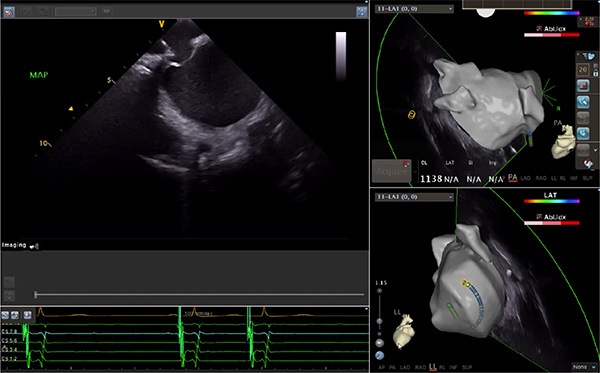

超聲心動圖技術包括常規(guī)經胸超聲(TTE)、經食管超聲(TEE)、心腔內超聲(ICE)、超聲聲學造影(MCE)、三維超聲心動圖等,ICE是一種新興技術——將微型的換能器安裝在心導管的尖端,經由外周血管輸送至心腔內部,換能器發(fā)射聲波,對心臟及其鄰近組織進行實時高質量成像和(或)血流動力學測定的超聲成像技術?;诓煌募夹g原理,心腔內超聲導管被分為兩類:機械旋轉式超聲導管和相控陣超聲導管。目前,臨床上主要應用的是相控陣超聲導管,ICE成像通過術者旋轉導管及操縱導管手柄上的兩個旋鈕來完成。

隨著心腔內超聲的應用更廣,性能也在逐漸優(yōu)化,已從二維成像轉變?yōu)?strong>三維成像,極大增強了引導及可視化能力。二維心腔內超聲支持雙平面或三平面成像,可顯示兩個或三個不同的平面視圖,但醫(yī)生需將這些圖像在腦海中重新構建為三維解剖結構。三維心腔內超聲則可直接呈現(xiàn)三維解剖結構圖,便于醫(yī)生更輕松地開展手術。按照產品發(fā)展方向,預計心腔內超聲還將向更清晰、精準、多功能等方向發(fā)展。